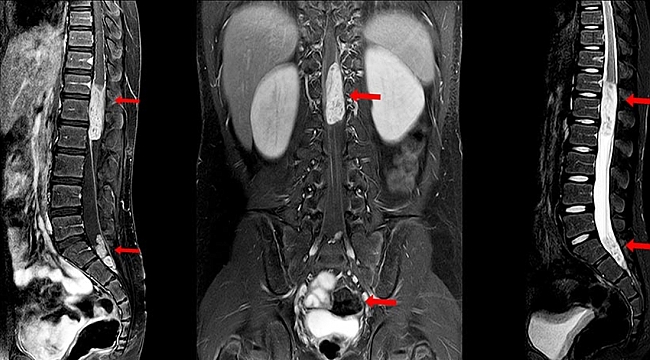

Yaşanan belirtiler hasta tarafından bel fıtığı gibi farklı rahatsızlıklarla karıştırılabildiği için doktora başvurma konusunda geç kalınabilmektedir. Doktor muayenesinin ardından Manyetik Rezonans (MR), Bilgisayarlı Tomografi (BT) ve röntgen gibi radyolojik görüntülemelerle şikâyete neden olan lezyon kolaylıkla belirlenebilmektedir. Omurga tümörü belirlendikten sonra kapalı biyopsi yöntemi ile tümörün tanısı konulabilmektedir. Ayrıca belirlenen lezyonun omurga kaynaklı primer tümör veya metastaz kaynaklı olup olmadığının belirlenmesi için PET CT görüntülemesi de yapılmalıdır. Omurgaya sık metastaz yapan meme, akciğer, prostat, tiroid gibi organlarında incelenmesi, bazı özel kan tahlilleri ile laboratuvar incelemelerinin yapılması da teşhis bakımından önemlidir.

Yaşanan belirtiler hasta tarafından bel fıtığı gibi farklı rahatsızlıklarla karıştırılabildiği için doktora başvurma konusunda geç kalınabilmektedir. Doktor muayenesinin ardından Manyetik Rezonans (MR), Bilgisayarlı Tomografi (BT) ve röntgen gibi radyolojik görüntülemelerle şikâyete neden olan lezyon kolaylıkla belirlenebilmektedir. Omurga tümörü belirlendikten sonra kapalı biyopsi yöntemi ile tümörün tanısı konulabilmektedir. Ayrıca belirlenen lezyonun omurga kaynaklı primer tümör veya metastaz kaynaklı olup olmadığının belirlenmesi için PET CT görüntülemesi de yapılmalıdır. Omurgaya sık metastaz yapan meme, akciğer, prostat, tiroid gibi organlarında incelenmesi, bazı özel kan tahlilleri ile laboratuvar incelemelerinin yapılması da teşhis bakımından önemlidir.